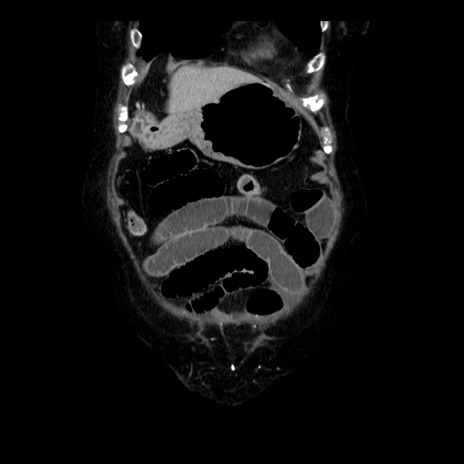

症例14(冠状断像)

【症例】 90歳代女性

【主訴】 腹痛・嘔吐

【現病歴】今朝から左側腹部痛を認めた。 経過観察していたが、嘔吐を認めたため来院。

【既往歴】 子宮癌術後

【身体所見】 意識清明、BP 127/54mmHg、P 98bpm Sp02 95%(RA)、BT 35.8°C、腹部平坦・軟腸ぜん動音聴取良好、右下腹部圧痛(+) 反跳痛なし

【データ】WBC 9800、CRP 0.46